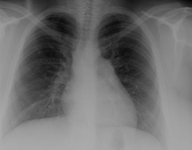

Radiografia torácica demonstrando a transposição circulatória pulmonar

Mayo Clinic Foundation